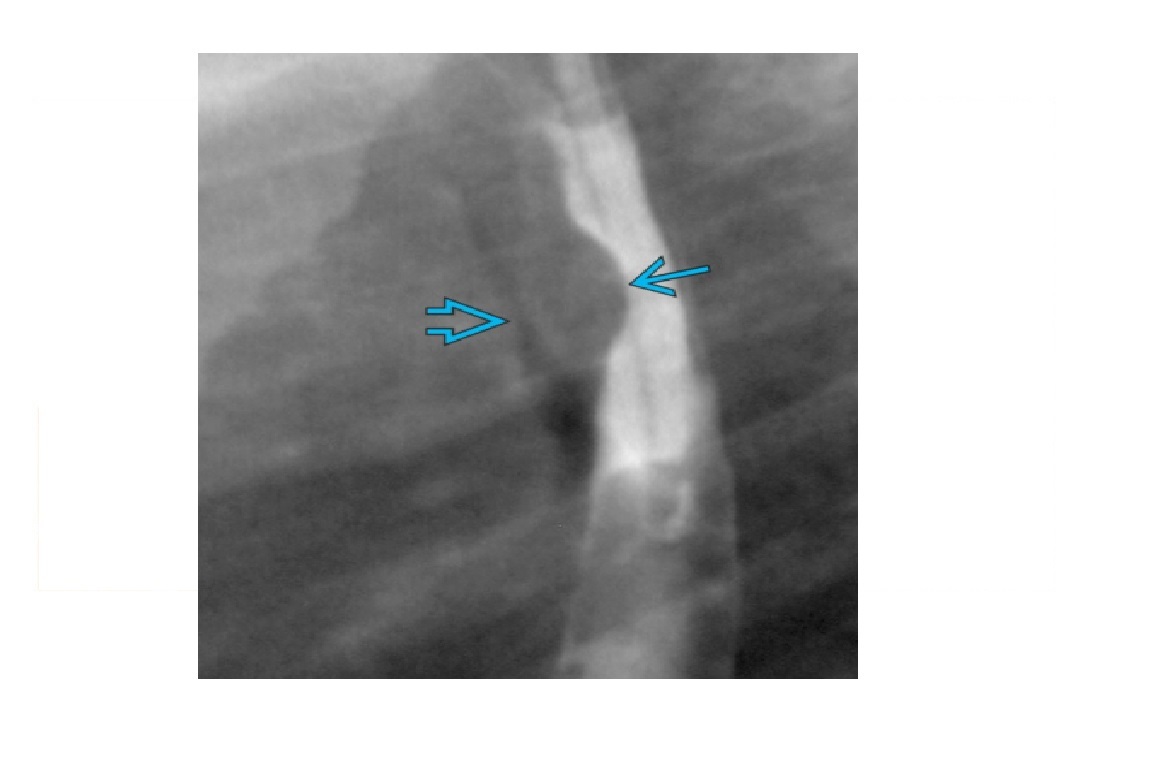

Chronic pancreatitis duct dilatation vs pancreatic malignancy duct dilatation?

CP - dilatation is irregular - Duct is <50% of the AP gland diameter Cancer - Dilatation is uniform - Duct is >50% of the AP gland diameter